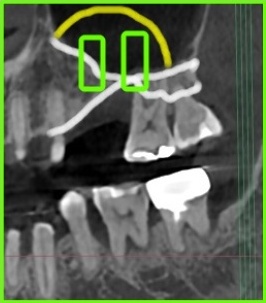

사진 2) 임플란트를 식립하려면(초록색 네모), 상악동 거상술을 통해 뼈를 만들어 줘야 합니다.(노란색 실선)

사진 3) 실제 임플란트를 식립하고 상악동 거상술 뼈이식을 완료한 상태입니다.(빨간색 점선)